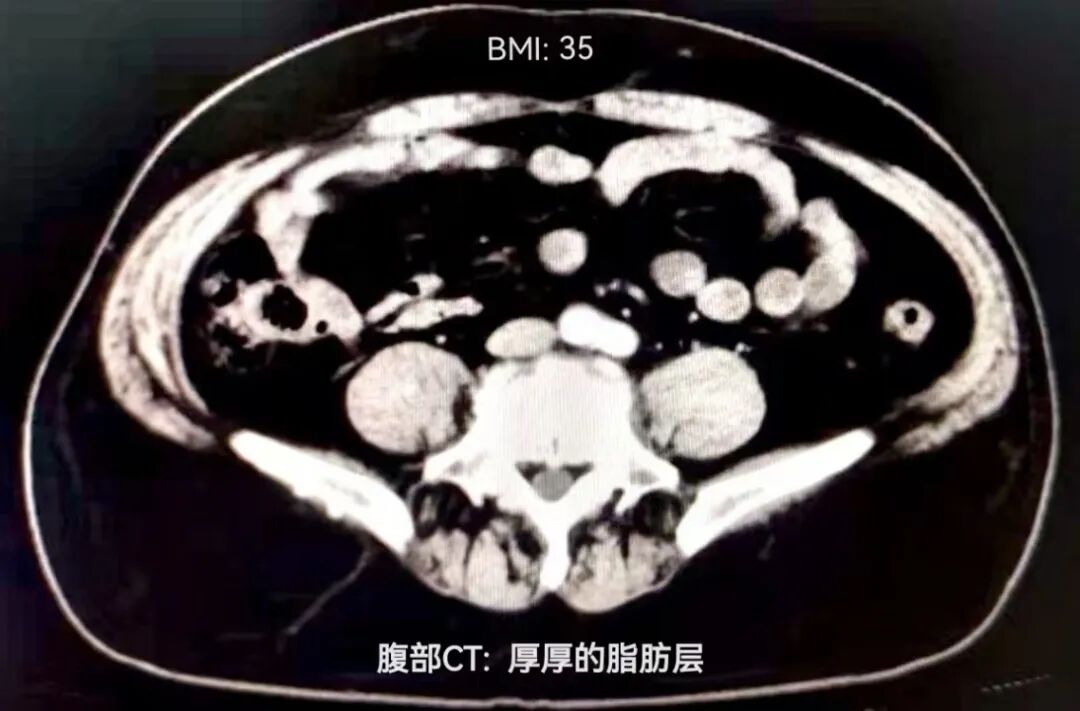

今年40岁的王先生(化名)体重近200斤,BMI指数(身体质量指数,计算公式为:BMI=体重÷身高的平方)超35,前段时间,他时常出现大便带血。开始他只当做痔疮发作,没有引起重视。近来,他发现自己腹部隐痛、排便规律也有改变,大便次数越来越多,意识到自己的身体可能出了问题,王先生遂来到通大附院就诊,后转到胃肠外科治疗。

(患者术前的CT检查显示腹部肥厚的脂肪)